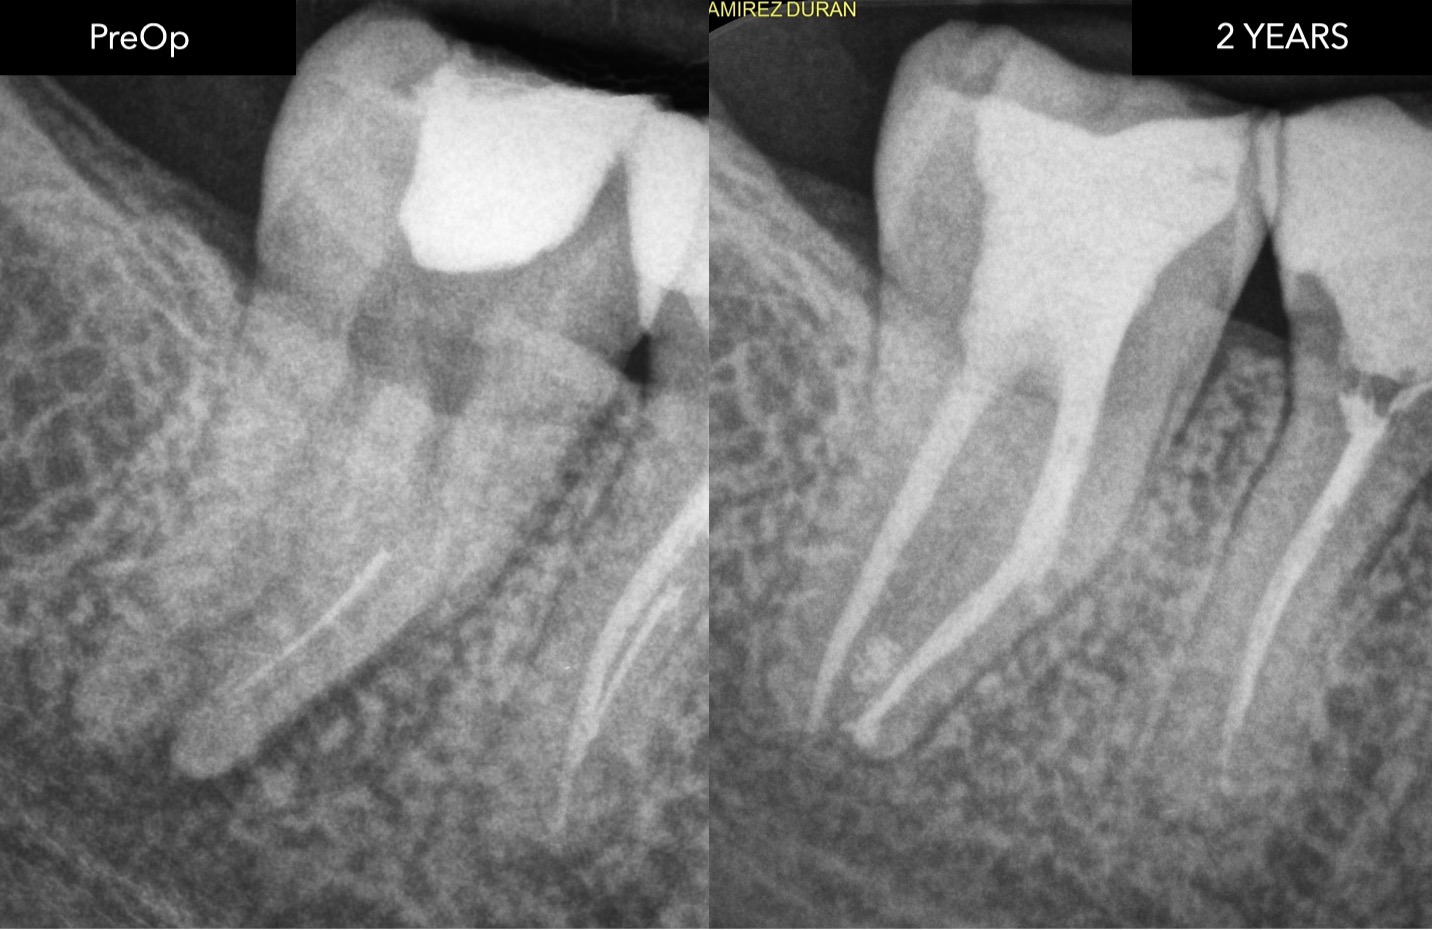

Healing dynamics and 2 years outcome

Following successful orthograde retrieval, the case was completed with three-dimensional cleaning and obturation of the root canal system.

The immediate postoperative radiograph shows an adequate obturation, respecting the original anatomy.

An angled radiograph was also taken to better assess the complexity of the mesial root system and confirm the quality of the treatment.

At the 1-year follow-up, a clear reduction in the periapical radiolucency can be observed, indicating favourable healing.

At 2 years, complete radiographic resolution of the lesion is evident, confirming long-term success.